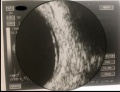

Fig. 1 Clinical presentation of IRU. Fig. 1A represents a fundoscopy with discrete vitritis, macular edema, optic disc pallor and peripheral atrophic chorioretinal scars with no signs of activity of CMVR in a patient with microscopic polyangiitis treated with mycophenolate mofetil referred for observation due to complaints of left reduced visual acuity and floaters that started ten months after suspension of immunosuppressive therapy due to CMV colitis. Fig. 1B shows the optical coherence tomography (OCT) of the same patient with cystoid macular edema.